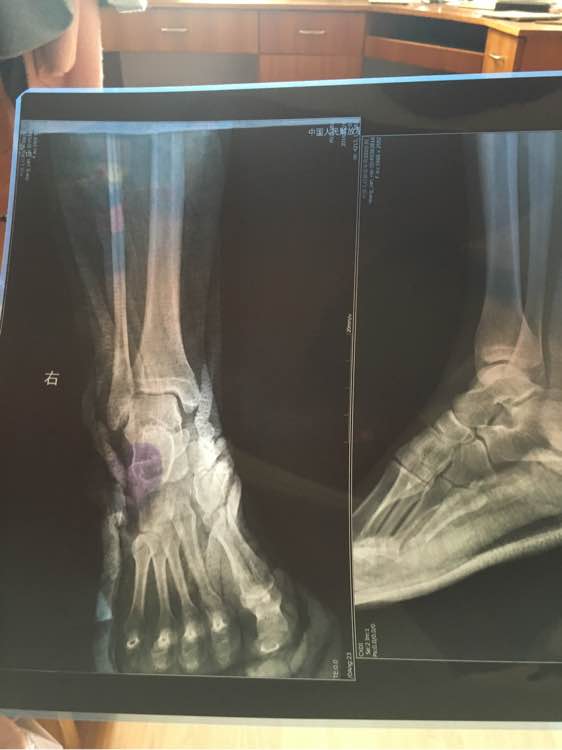

右踝轻微骨折,一个月,昨天复查拍的片子

这是我一个月复查的片子

这是我骨折后一个星期拍的片子

小的是一个星期拍的,大的是一个月拍的

还有最后一张,刚骨折拍的,我感觉从刚骨折到一个月复查,没多大问题,到一个月骨缝越看做清楚了怎么回事

这感觉我都不知道我到底好了多少,从刚开始看不出来到现在看的出来

回复 多多是小坏蛋 :你这照片,脚的角度不一致,尺寸大小不同,大的就清楚点,小而模糊,